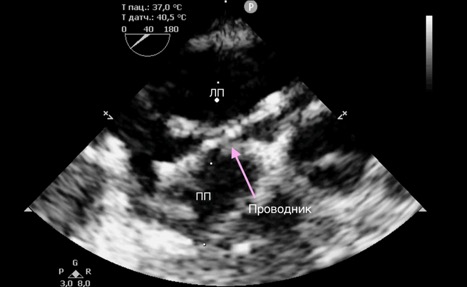

После достижения необходимой анестезии устанавливали интродьюсер, через который в правое предсердие вводился проводниковый катетер. Наведение проводника на межпредсердную перегородку осуществлялось под контролем чреспищеводной эхокардиографии. В большинстве случаев выбирали область овальной ямки (лат. fossa ovalis) как наиболее анатомически безопасную и предсказуемую зону для пункции. Пункция перегородки выполнялась обратной (тупой) стороной проводника, что снижало риск повреждения окружающих структур (рис. 2). После успешного проникновения в левое предсердие по проводнику заводился баллонный катетер (диаметром от 12 до 14 мм).